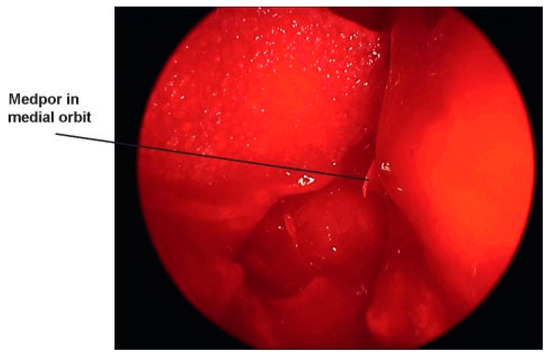

Medial orbital fractures are treated similarly to floor fractures except that these require more extensive knowledge of intranasal anatomy. To undertake the endoscopic repair, you must be aware of endoscopic skull base anatomy and be comfortable taking or medializing the middle turbinate and taking the uncinate process and ethmoid bulla down (Figure 8). If you can do this, you can have a full view of the lamina papyracea (Figure 9). Once the lamina is identified, you can ballot and find the defect. This is then most easily repaired with a Silastic sheet of sufficient stiffness to prevent herniation of the orbital contents. A thin Medpor sheet may also be used (Figure 10).

Figure 8. Medial wall fractures are essentially an extended ethmoidectomy and placement of a Silastic sheet. This is a view of the septum to the left, inferior turbinate takeoff below, and the middle turbinate to the middle of the screen.